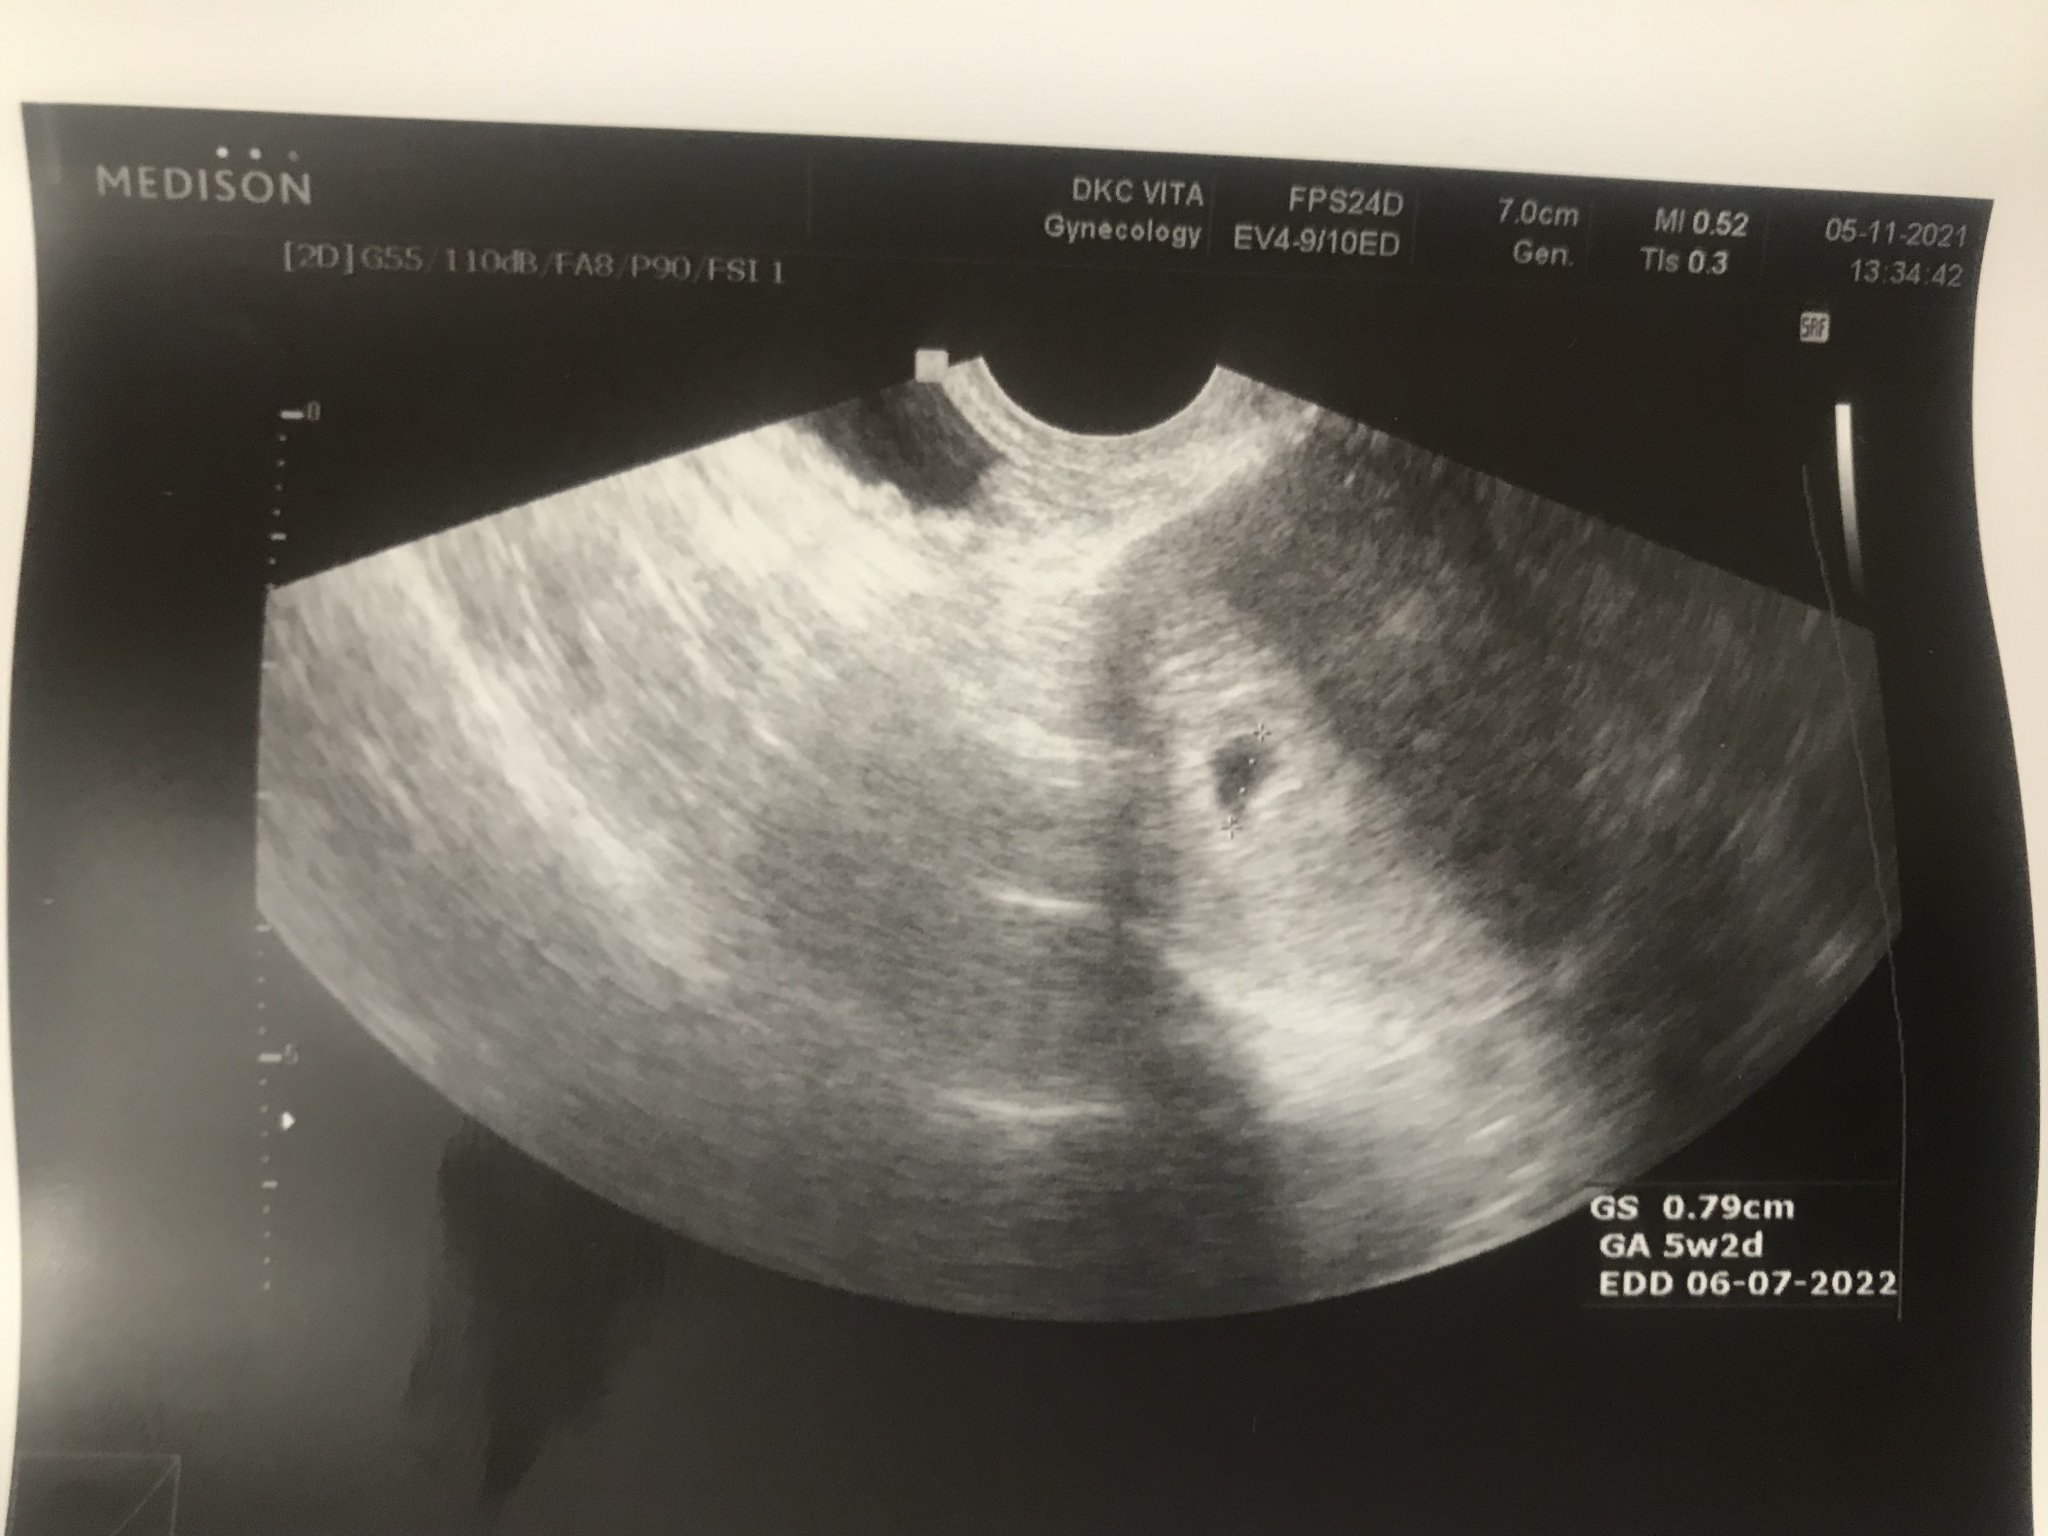

Какви са препоръчителните тестове по време на бременност и какви са разликите между биохимичния скрининг (БХС) и ДНК теста?